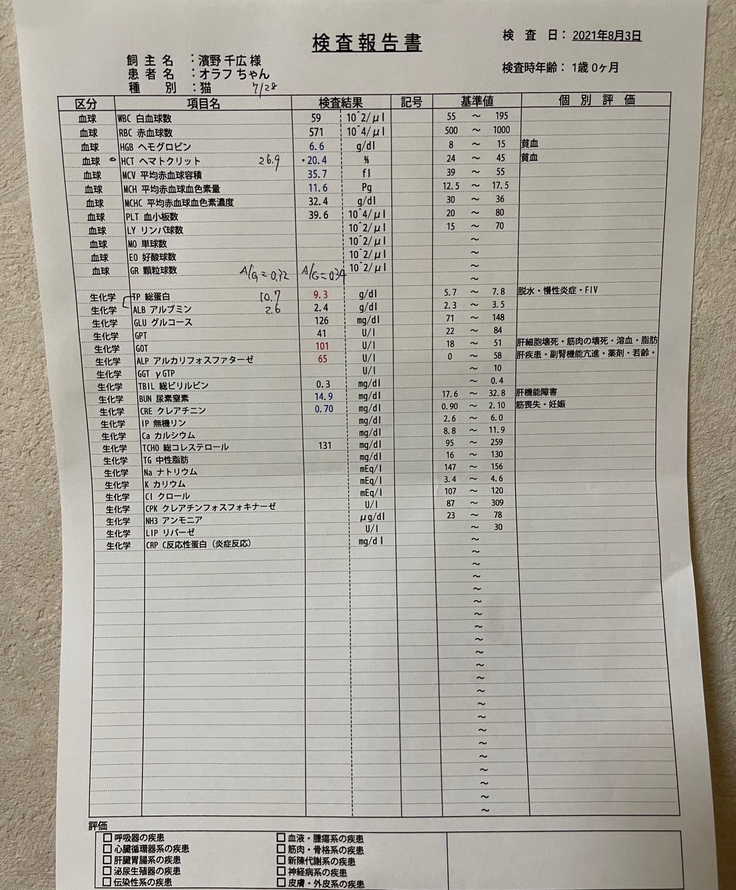

★薬代 8/3~8/26 12,375円(450mg)×24日

8/27~10/3 13,750円(500mg)×38日

10/4~10/25 15,125円(550mg)×22日

84日間の合計1,152,250円です。

★検査費等 85,382円

これまでのFIP治療費は1,237,632円です。

血液検査、超音波検査、FIP検査、細胞診を行いました。

オラフのFIP陽性の検査結果が出ました。

炎症度合いの数値も2000以上と正常値ではありませんでした。

FIP陽性が確定し、オラフの動きは悪くはなかったんですが、食欲は戻らなかったので再度B病院に行きました。

熱が40度あり、体重が3.3kg→3.0kgまで減っていました。

血液検査の結果も前回より貧血値やA/G比が悪くなっていました。

「新薬に切り替えたほうがいいです。」と言われました。

そしてこの日からオラフの84日間の投薬が始まりました。

検査費と薬代です。